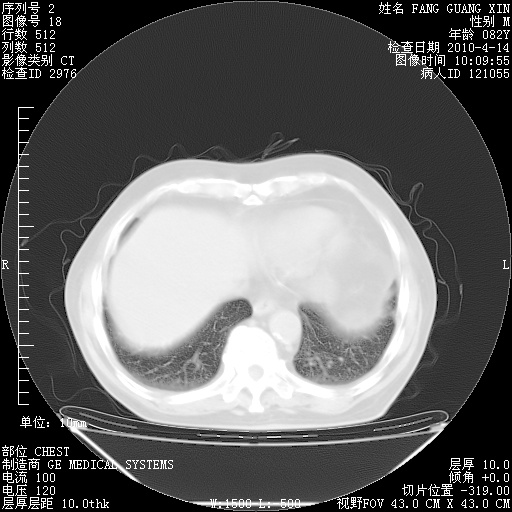

4月14日肺部CT

肺部CT平扫未见异常。